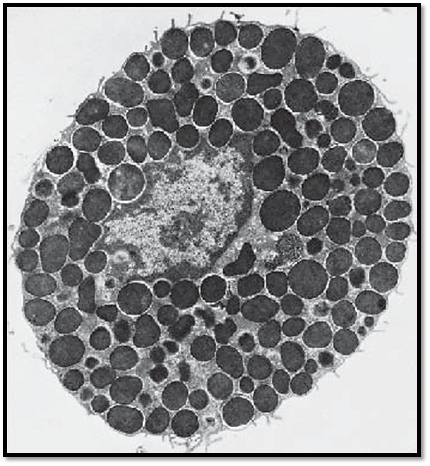

This transmission electron microscopic image displays the typical ultrastructure of a tissue mast cell from a rat. On the surface are sporadic short plasma membrane processes. The central nucleus is relatively small and shows peripheral heterochromatin. The nucleus is dente d in several places because of the close vicinity to cell-specific granules. The cytoplasm contains the specific round or oval granules, which have diameters of about 0.5–1.5 μm. The granules are always enclose d by a membrane and separate d from other granules by cytoplasmic septa, which contain crista-type mitochondria, Golgi complexes and, sporadically, filaments. The matrix of each granule is homogeneous and electron-dense. Based on their sulfate d glycosaminoglycan content, mast cells show a meta-chromatic reaction—i.e., their granules appear between blue-violet and re d after staining with a blue alkaline thiazine dye. The granules contain heparin and the biogenic amine histamine. Heparin inhibits blood clotting and is a potent anticoagulant. Histamine causes the arteries and arterioles in connective tissue to dilate. There are two different types of mast cells—the tissue mast cells in the connective tissue of the skin and the mucosa mast cells in the connective tissue of mucous membranes.

Electron microscopy; magnification: × 11400